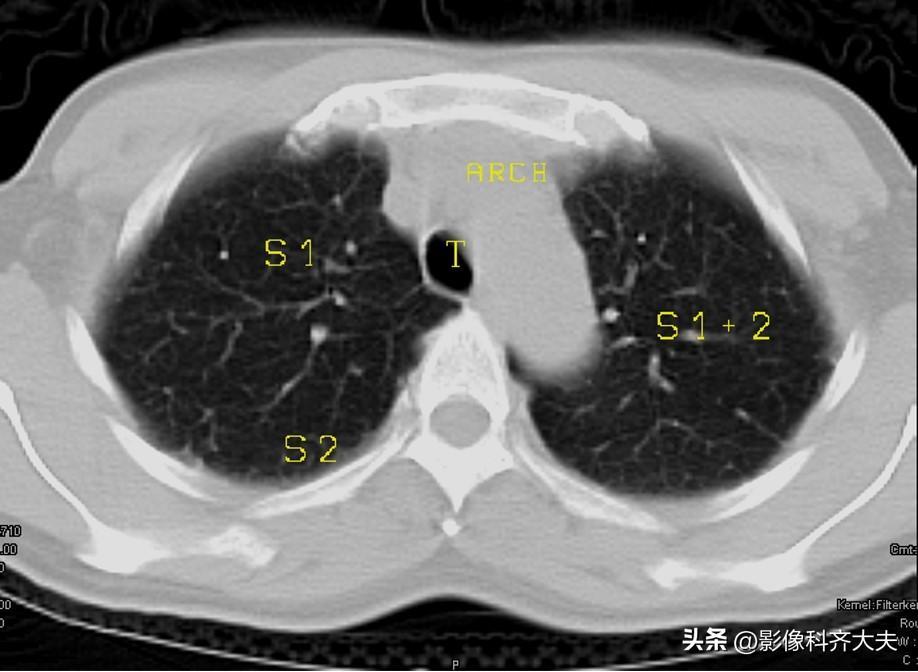

图1-胸锁关节层面

▲T:气管,E:食管,S1:上叶尖段